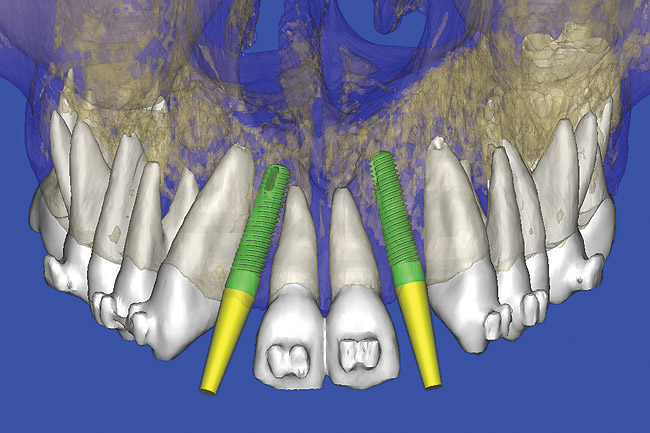

After the basic plan had been established, it was re-evaluated using interactive 3D images. The reconstructed 3D view of the maxilla clearly illustrated the extent of the bilateral facial concavities, and the root eminences of the adjacent and posterior teeth (Figure 12). The placement of the virtual implants then was evaluated to ensure that the facial cortical plate was not perforated (Figure 13). The implants were labeled individually as “7” and “10,” with the simulated yellow abutment projection indicating the facial-lingual inclination through the bone to the level above the incisal edge of adjacent teeth. The ability to gain a better understanding of these individual root forms cannot be underestimated. The dental literature has suggested certain parameters for placing implants near teeth and implants next to other implants. However, there is little scientific 3D documentation to support these suggested rules.5-10 The use of an interactive treatment-planning software application permits closer scrutiny of previously difficult-to-visualize areas, and can now be used to redefine perceptions of spatial positioning of implants, especially when in close proximity to natural tooth roots, vital anatomy, and adjacent implants.27-29

Using different masking (segmentation) and threshold Hounsfield unit values, several new 3D bone volumes can be created which offer invaluable information. To help determine the final position of each implant a new bone model was created with a Hounsfield unit value of 1480, which eliminated all but the densest objects included in the scan data. (Results may vary depending on the CBCT machine used.) The inner and outer layers of bone were removed, leaving the underlying enamel and root structure of the teeth (Figure 14). After the bone had been stripped away, the root inclinations were examined closely. The most striking findings confirmed the rotated position of the right central, while revealing the slight mesial dilaceration of the root apex, which converged on the space needed for the path of the potential implant (Figure 15). The schematic shapes of the proposed implants were visualized for the right and left lateral spaces in different rotations of the 3D maxillary arch. It was at this point that a determination was made as to the appropriate implant shape and type that would fit the available space while avoiding encroachment on adjacent tooth roots. A tapered design implant (Tapered Screw-Vent®, Zimmer Dental, www.zimmerdental.com) was chosen from the large virtual library. With the SIMPlant software, the virtual library contains data from dozens of implant manufacturers and realistic computer-aided design representations as seen in Figure 16 through the translucent bone. The position of the left implant can be visualized with adequate mesial-distal distance between adjacent tooth roots (Figure 17) and a more delicate placement (Figure 18).

Figure 12  SOFTWARE IMAGING The 3D reconstruction showed the facial concavities and root eminences.

Figure 12

Figure 13  SOFTWARE IMAGING This allowed for evaluation of virtual implant placement to ensure the facial cortical plate was not perforated.

Figure 13